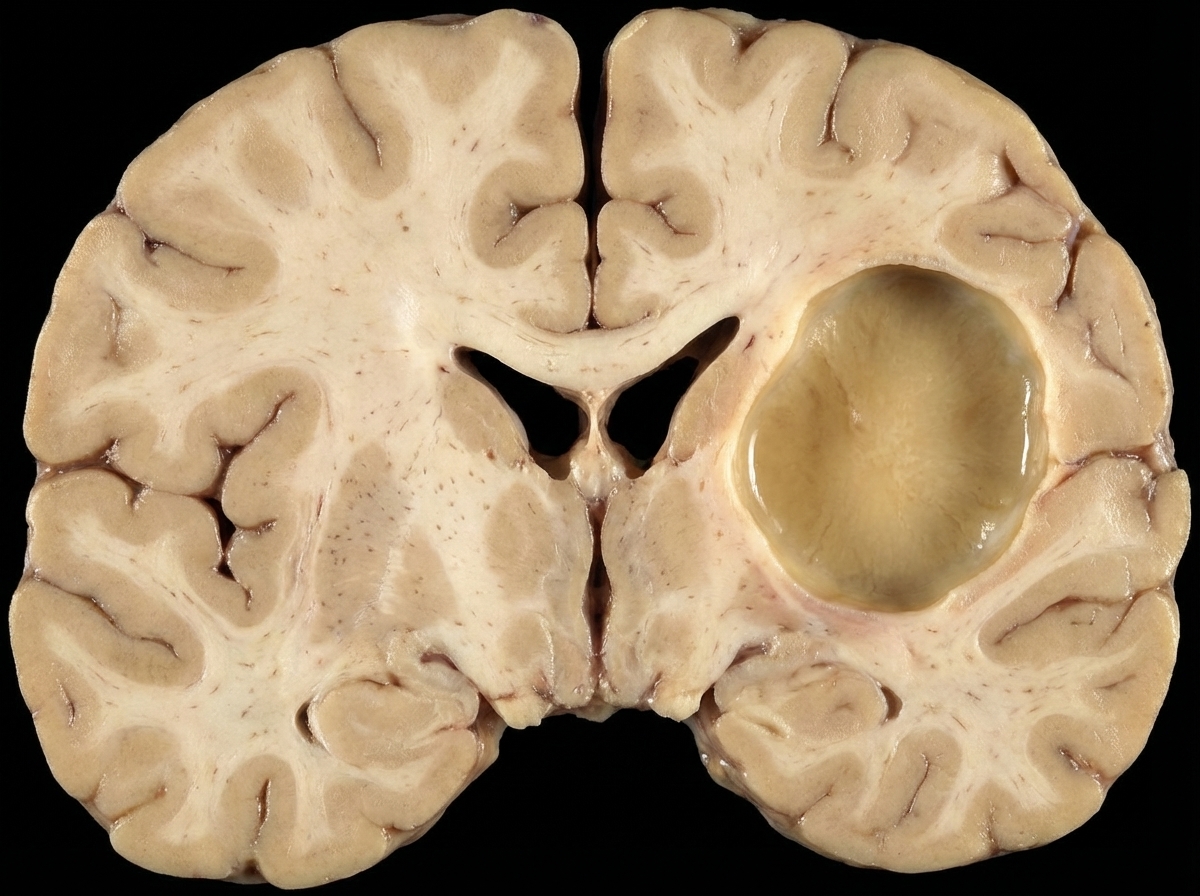

The given lesion is best associated with which of the following conditions?

Explanation: ***Atherosclerotic (ischemic) stroke*** • The large **cystic cavity** with **liquefactive necrosis** in the **MCA territory** is characteristic of a chronic atherosclerotic infarct where necrotic tissue has been cleared. • **Single-territory involvement** and the **well-demarcated** nature of the lesion strongly suggest **thrombotic occlusion** of a major cerebral artery due to atherosclerosis. *Embolic stroke* • Typically produces **multiple small infarcts** scattered across different vascular territories rather than a single large cavity. • Often shows **hemorrhagic transformation** with petechial bleeding, which is not evident in this purely cystic lesion. *Hypertensive bleed* • Usually occurs in the **basal ganglia**, **thalamus**, or **brainstem** due to rupture of small penetrating arteries. • Presents as **acute hemorrhage** with blood clot formation, not as a **cystic cavity** with liquefactive necrosis. *Ruptured berry aneurysm* • Causes **subarachnoid hemorrhage** with blood in the **subarachnoid space** around the brain surface. • Does not typically produce **parenchymal cystic cavities** but rather results in **acute bleeding** into CSF spaces.